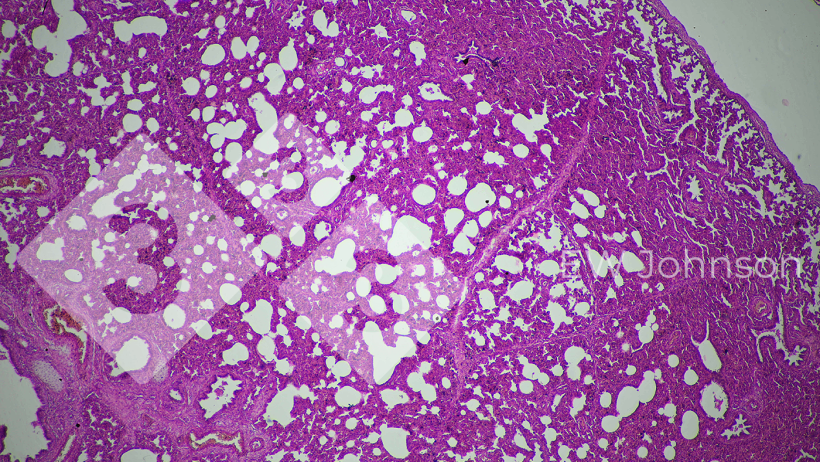

La PCR s'est révélée négative pour le SDRP, la pseudorage (PRV, maladie d'Aujeszky), les circovirus porcins PCV2 et PCV3, la peste porcine classique (PPC) et la peste porcine africaine (PPA). L'exploitation était connue pour être indemne de SDRP, de PRV, de peste porcine classique et de peste porcine africaine avant cet événement. La PCR pour le Getahvirus dans les poumons des porcelets s'est révélée hautement positive. L'histopathologie a révélé une pneumonie interstitielle sévère (figure 3) et une méningo-encéphalite fibrinohémorragique (figure 4). La maladie périnatale à virus Getah a été diagnostiquée. L'élevage a été informé que cette maladie est principalement transmise par les moustiques et des mesures de contrôle ont été mises en œuvre. Il n'y a pas eu d'autres cas ou signes cliniques dans l'élevage et la production est revenue à la normale.

Figure 3 : La pneumonie interstitielle suggère une origine virale possible.